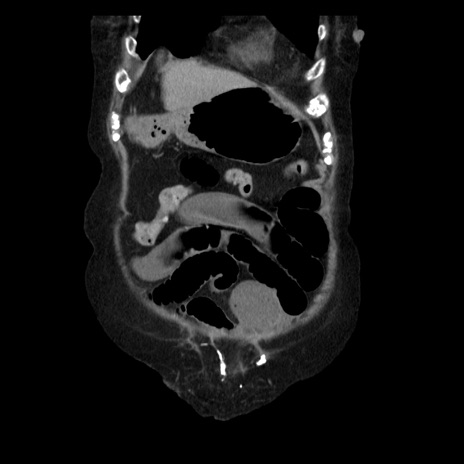

横断像